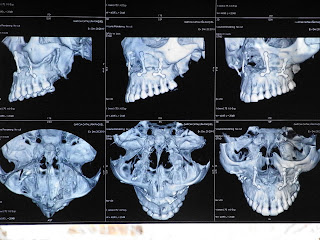

El martes me hicieron de nuevo la traca de pruebas, esta vez con un extra (de navidad) un TAC, a la espera de decidir cosas y ver como iba reposando el mundo en mi interior.

3D (y sin gafas) al alcance de los dientes.

Me sigue dando cierta grima cuando los miro, y eso que son mios.

Parece que todo está en su sitio... las placas, los tornillos... viva la era del metal (sin olvidarnos de la fusión con la era del plástico, que una es moderna y puede hacer espuma de titanio) Lo que más me impresiona es ver el corte y el desplazamiento... he tenido que esperar siglo y medio para poder entender bien la operación... si lo sé pido antes el TAC.

Ahora que ya me he vuelto experta de palo en medicina improvisada puedo adelantaros la pregunta de turno: ¿Donde esta Wally? ¿Qué hay diferente entre el lado derecho y el lado izquierdo? ¿Te dejo unos segundos más para pensar?

BINGO!!! uno está lleno y el otro vacío. Muy bien... ya tienes el titulo de médico de palo en prácticas. (Si averiguas lo que conlleva antes de seguir leyendo la página reclama tu fonendo de cartón piedra apto para uso casero)